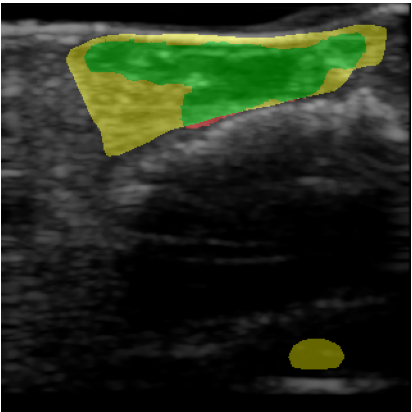

For quantitative evaluation of the network, we calculated precision, recall and the Dice score, also known as F1 score, of the network prediction compared to the GT annotation. Results are also visualized to compare GT with the network prediction. True positive (TP) pixels are colored green, false positives (FP) are colored yellow, false negatives (FN) are colored red and true negative (TN) areas are transparent.

Figure 2: (a-d) Four representative US wound images. (e-h) Visualization of corresponding segmentation predictions for FCN. Green indicates correct matches, red and yellow indicate missed (false negative) and oversegmented (false positive) areas, respectively.

Table 2 shows the quantitative evaluation of the algorithms. U-Net and FCN both achieve a Dice score of 0.340.340.34 compared to pre-trained ResNet-U-Net which has a Dice score of 0.270.270.27. Visualizations of the segmentation results for FCN are shown in Figure 2, where (a-d) are the original inputs, and (e-h) the corresponding color-coded outcomes. In general, the performance is promising for a number of cases, although we see a high FP rate (d,h) for others. Table 3 shows the ratio of m¯rsubscript¯𝑚𝑟\overline{m}_{r} for different wound regions compared to m¯wsubscript¯𝑚𝑤\overline{m}_{w} of the whole wound area. In the wound center, the US values are lower (ratio: 0.89 ±plus-or-minus\pm 0.11), compared to the wound borders (ratio: 1.47 ±plus-or-minus\pm 0.37).

In this work, we showed a proof-of-concept for a non-invasive imaging technique paired with machine learning. We performed initial experiments for automatic segmentation of US wound images with deep learning which show an Dice score of 0.340.340.34 for both U-Net and FCN and 0.270.270.27 for ResNet-U-Net. The segmentation results strongly depend on the quality of the scan and the specific wound type. Quantitative results can still be improved but the visual examination of the results indicates applicability of the proposed setup. For images illustrated in Figure 2(e-g), the segmentation is very good. However, the network misclassifies the region beneath the hyperechoic bone surface (image h) as this region therefore appears dark and similar in intensity to the wound region.